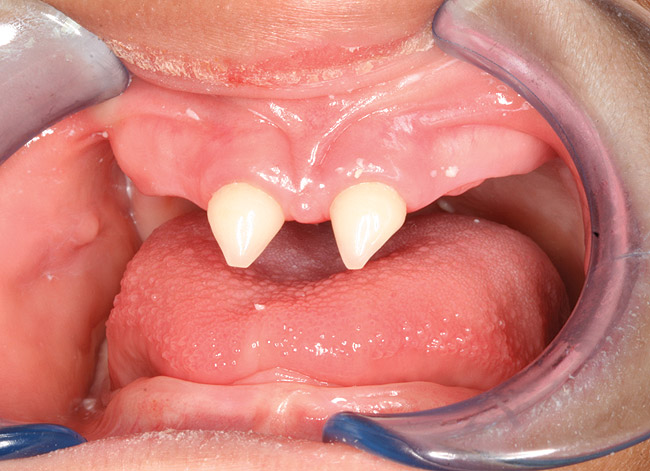

The following case report shows the systematic application of the above-mentioned principles. A 5-year-old male who had received a diagnosis of hereditary hypohidrotic ED was presented by his mother, who stated that she wanted his teeth to appear normal for school (Figure 1 and Figure 2). On clinical and radiographic examinations, it was noted that the patient had anodontia in the mandible, only two erupted primary incisors in the maxilla, and three developing tooth buds in the maxillary anterior region. Alveolar bone was significantly deficient (Figure 3). The erupted maxillary incisors had the characteristic cone shape (Figure 4). The patient presented with a knife-edge shaped mandibular residual ridge and significant xerostomia (Figure 5). After evaluating the patient’s financial, social, and oral status, the authors developed a treatment plan that involved fabrication of maxillary and mandibular complete dentures. It was decided to perform endodontic therapy on the two maxillary incisors and reduce them to the gingival level for their use as overdenture abutments. The root canals were filled with silver amalgam up to 3 mm inside the canal space (Figure 6).

Figure 6  Maxillary alveolar ridge after endodontic therapy and crown amputation of the maxillary central incisors.

Figure 6